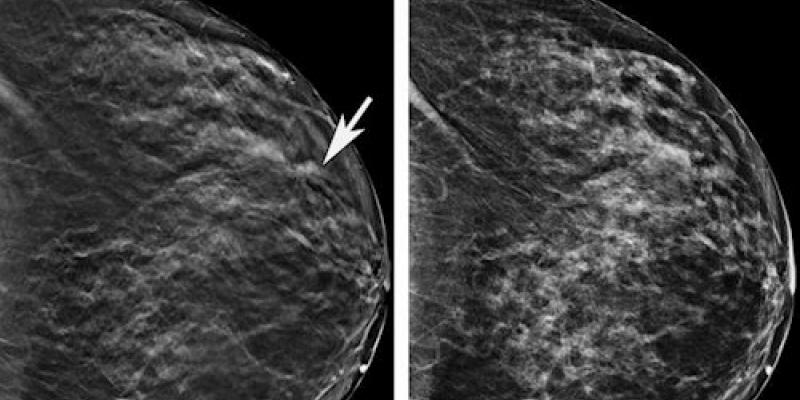

La mamografía 3D puede detectar hasta un 65 por ciento más de casos de cáncer de mama invasivo de forma precoz. Esta prueba evita la realización de otras pruebas adicionales. Además, cuenta con una precisión superior a la mamografía 2D en mujeres con mamas densas.

Así lo destacaron este martes en Madrid los radiólogos en el encuentro ‘Screening con tomosíntesis, ¿a qué esperamos? ¿qué nos falta?’. Allí se analizó el uso de la mamografía 3D en el cribado del cáncer de mama.